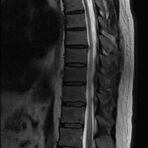

Wirbelsäule

• Abklärung Bandscheibenvorfall

• Beurteilung Einengung des Rückenmarkkanals oder der Neuroforamina im Rahmen der degenerativen Wirbelsäulenerkrankung

• Tumor-/Entzündungsdiagnostik

• Multiple Sklerose

• Abklärung Spondylolisthesis

• Frakturdiagnostik (Alter und Ausdehnung der Fraktur) z.B. im Rahmen der Osteoporose